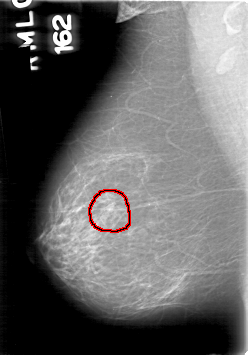

D_4094_1.RIGHT_MLO

RIGHT_MLO LINES 5311 PIXELS_PER_LINE 3706 BITS_PER_PIXEL 12 RESOLUTION 43.5 OVERLAY

FILE: D_4094_1.RIGHT_MLO.OVERLAY

TOTAL_ABNORMALITIES 1

ABNORMALITY 1

LESION_TYPE MASS SHAPE ROUND MARGINS OBSCURED

ASSESSMENT 0

SUBTLETY 4

PATHOLOGY BENIGN

TOTAL_OUTLINES 1

BOUNDARY